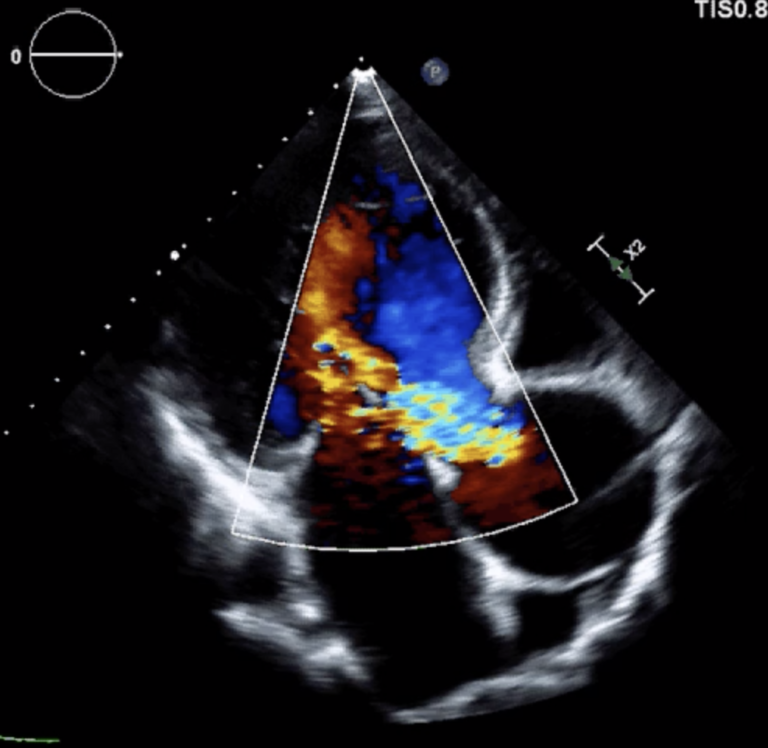

図1;大動脈弁閉鎖不全症の心臓エコー検査

大動脈弁の構造が壊れているため、高度の逆流を生じています。